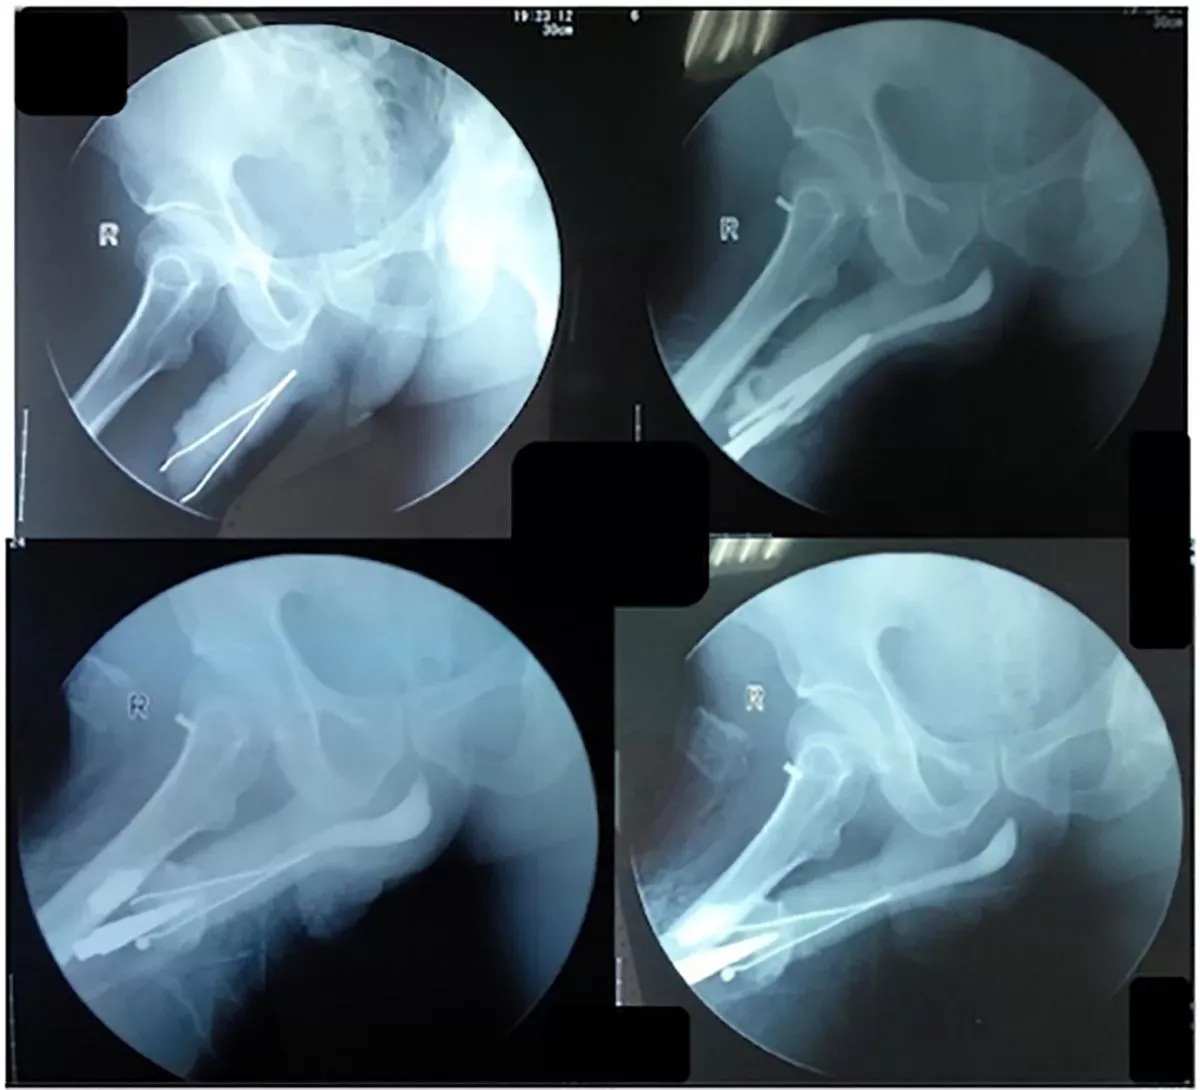

更離奇的是,男子的生殖器雖然卡了一把鉗子,但他仍能正常排尿,也沒有流血,只是每次上廁所時都會痛到慘叫,直到受不了才求醫。為取出異物,醫生先麻醉病人再執行移除手術。

病人要先麻醉再接受手術